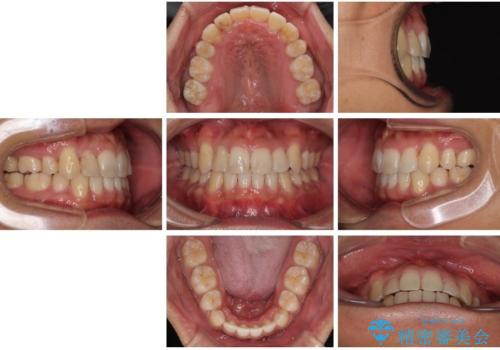

八重歯と前歯のガタガタを抜歯矯正で治療|クリアブラケット使用例

- 「八重歯を治したい」とご相談いただいた患者様の症例をご紹介します。

上下の前歯部に強い叢生(ガタガタの歯並び)があり、そのまま歯を並べると出っ歯になってしまう可能性がありました。

そこで、上下左右の第一小臼歯を抜歯し、歯が並ぶためのスペースを確保し叢生を解消する治療計画を立てました。

矯正装置は、審美性と費用面のバランスを考慮して、プラスチックブラケットとメタルワイヤーを使用しました。

透明感のあるブラケットを用いたため、従来の金属装置よりも目立ちにくく、日常生活での見た目の不安も軽減できます。

八重歯はきれいに整い、前歯もバランスよく収まり、横顔のラインも自然に改善されました。

治療後、患者様は「思い切り笑えるようになった」と大変喜んでくださいました。